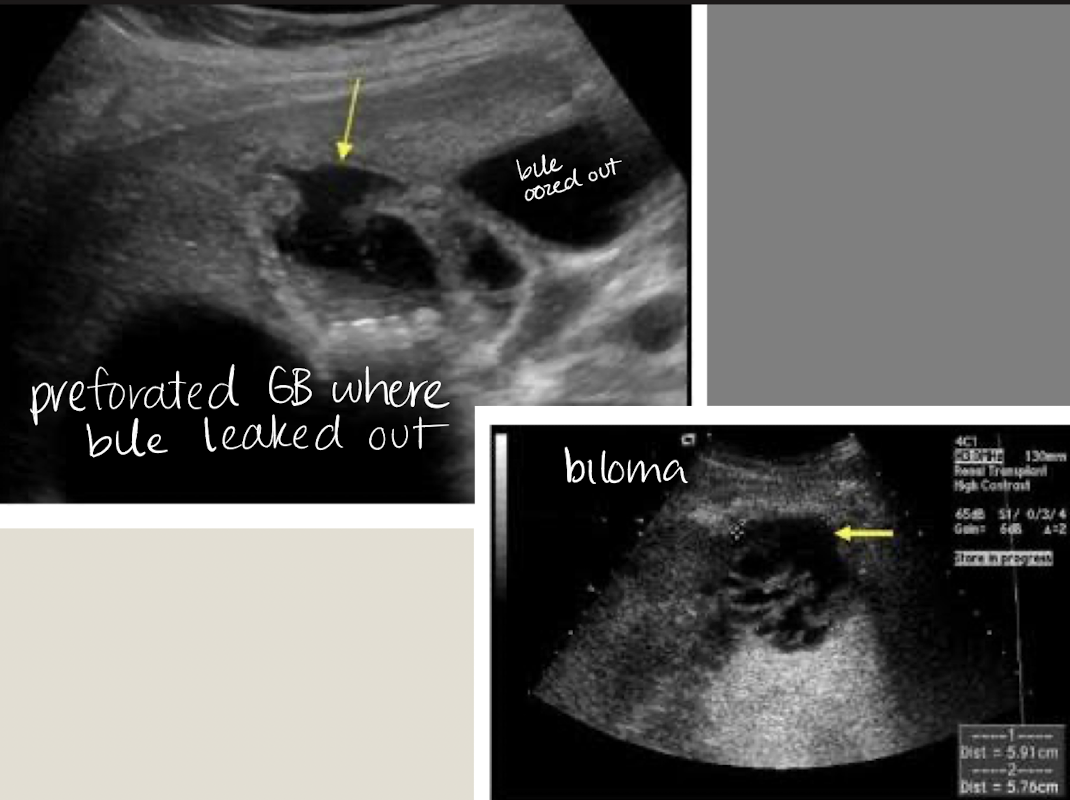

cholecystectomy

removal of GB —>

sphincter of Oddi loses tonus

bile flows freely into duodenum (biloma)

extrahepatic bile ducts dilate, up to 1 cm

what are some post complications of cholecystectomy?

biloma

stones

abscess

??